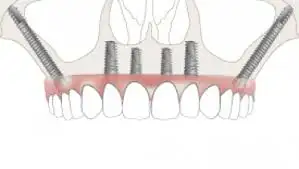

Tubero pterygoid implants are indicated for patients who do not have enough bone for regular conventional implants. These implants are placed in the 2nd and 3rd molar region of the upper jaw.